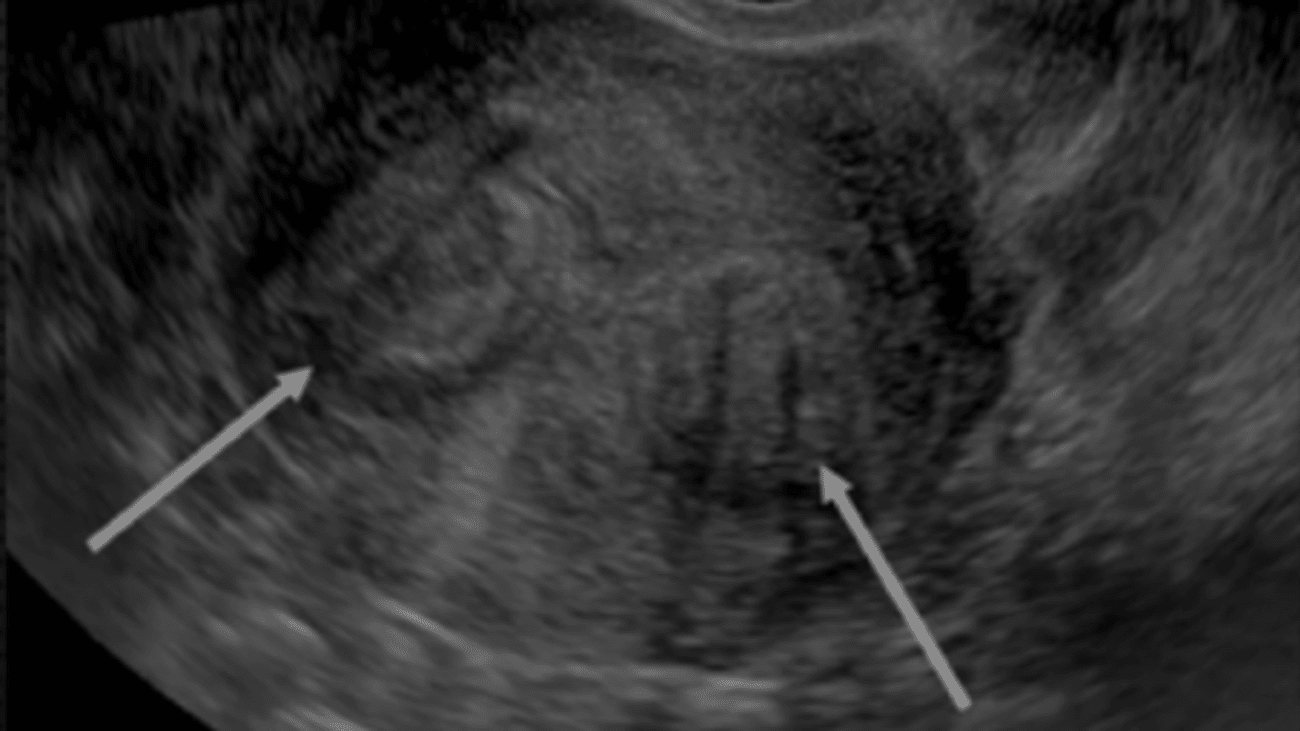

From ultrasound-images.blogspot.com

Ultrasound imaging Small pedunculated fibroid Heat And Fibroids There are many things you can do to take care of yourself if you have uterine fibroids. Michelle louie, a mayo clinic gynecologic surgeon and fibroid specialist, says there's a newer nonsurgical procedure to remove fibroids. Small incisions are made in the abdomen so your healthcare provider can access the fibroids and protect the surrounding healthy tissues (e.g., ovaries, uterus).. Heat And Fibroids.